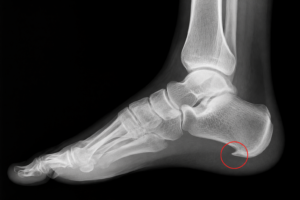

Ostroga piętowa leczenie to temat, który interesuje wiele osób zmagających się z przewlekłym bólem stopy. Schorzenie to rozwija się na skutek przeciążenia rozcięgna podeszwowego i prowadzi do powstawania bolesnej narośli kostnej. Odpowiednio dobrana terapia oraz produkty medyczne mogą znacząco przyspieszyć powrót do komfortu chodzenia.